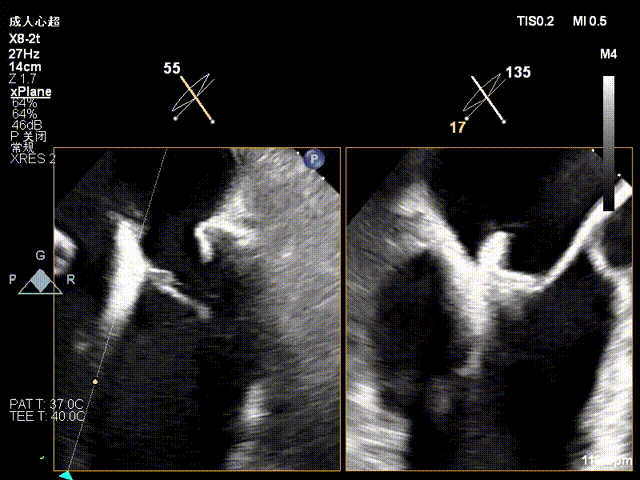

术前X-plane

术前X-plane上彩